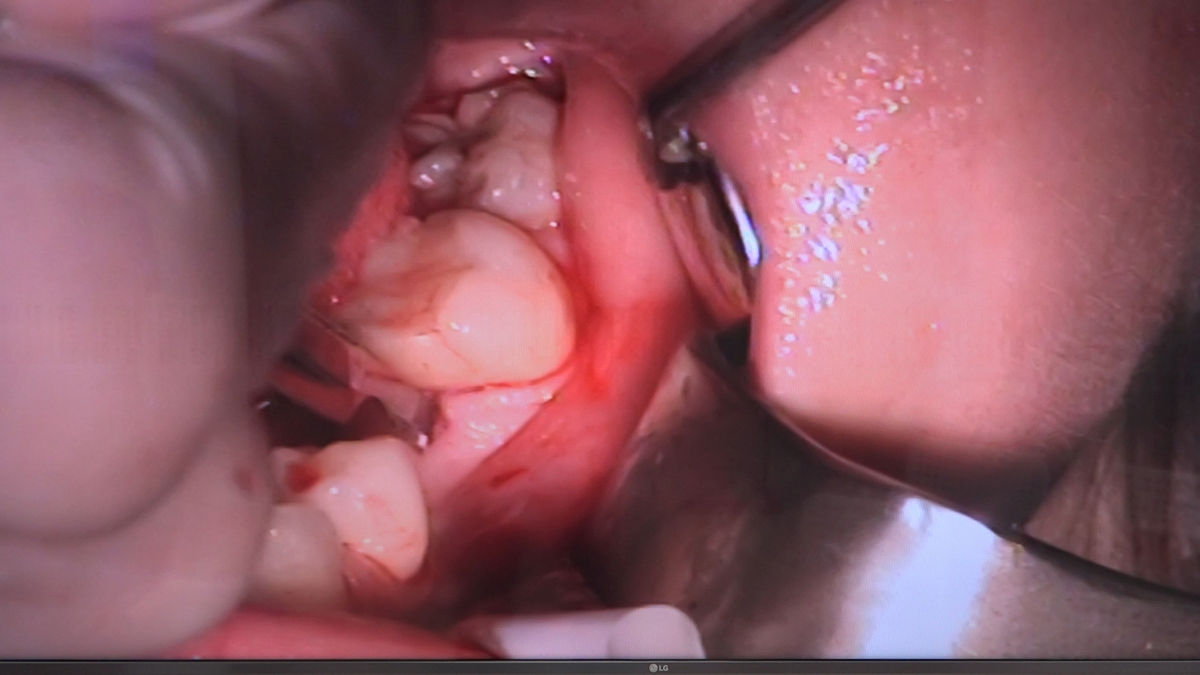

Chirurgia implantologiczna to temat wiodący 5 Sesji X Sezonu Practiculum Implantologii, która się odbyła 23-24 października 2020 roku. Bierze w nim udział 16 adeptów implantologii stomatologicznej. Zabiegi z udziałem Pacjentów jak zwykle poprzedziło omówienie i planowanie, tym bardziej, że zgodnie z planem wykonana została implantacja z wykorzystaniem szablonu chirurgicznego, który przygotowało laboratorium dentystyczne Wiligała Lab. Kursanci wykonywali szereg zabiegów implantologicznych i chirurgicznych oraz regeneracyjnych z zastosowaniem PRF, w tym sinus lift. Przeprowadzali je pod kierunkiem Lidera Umiejętności Implantologicznych dr n.med. Violetty Szycik, która wysoko oceniła wykonanie zabiegów.